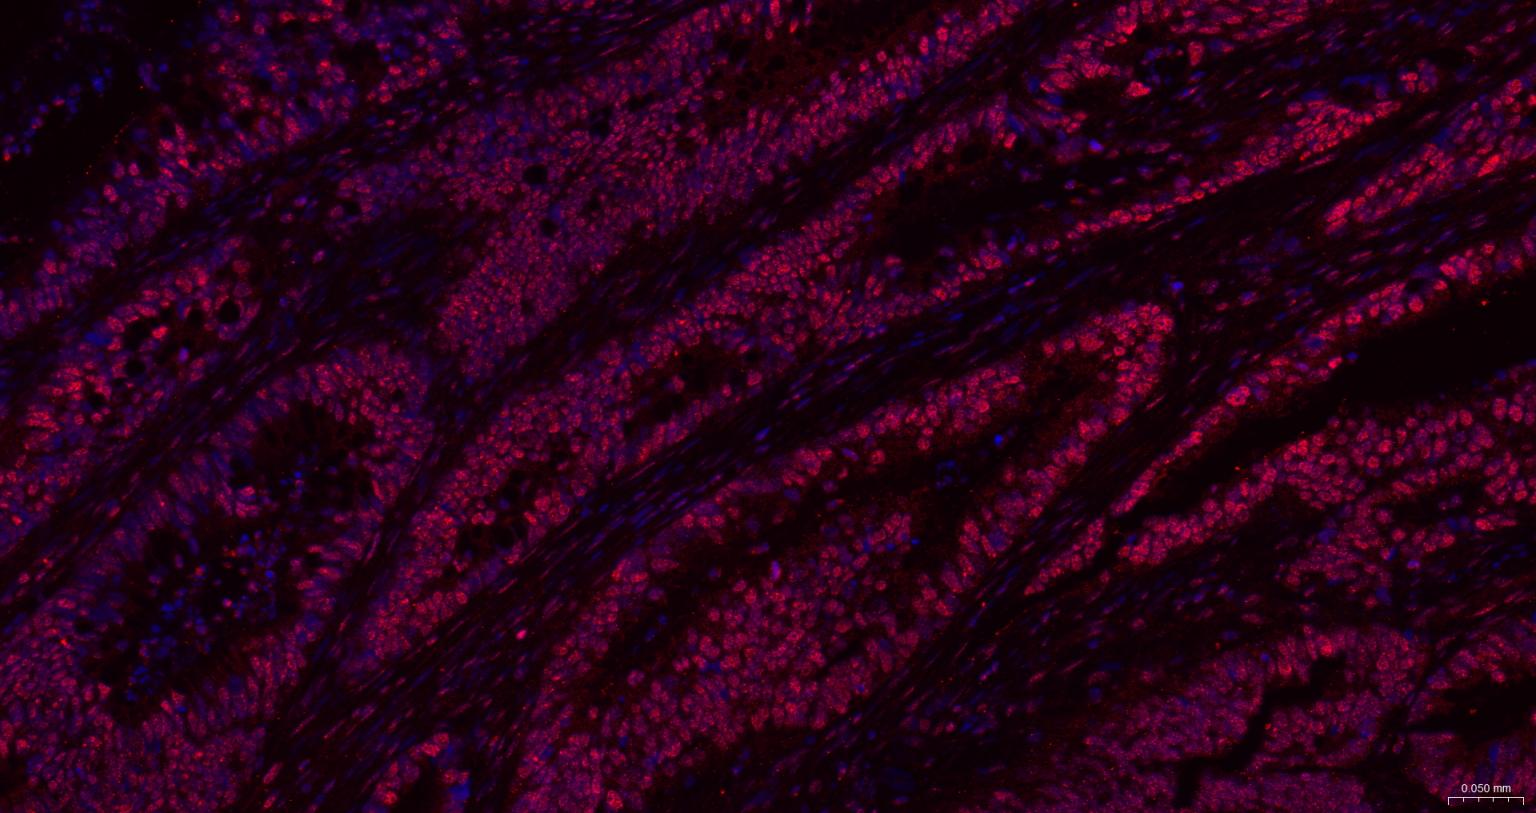

Paraformaldehyde-fixed, paraffin embedded Human Colon Cancer; Antigen retrieval by boiling in sodium citrate buffer (pH6.0) for 15 min; The section was incubated with CIDEC Polyclonal Antibody, Unconjugated (bs-6796R) at 1:200 overnight at 4°C. Followed by conjugated Goat Anti-Rabbit IgG antibody (Red, bs-0295G-BF594), DAPI (blue, C02-04002) was used to stain the cell nuclei.